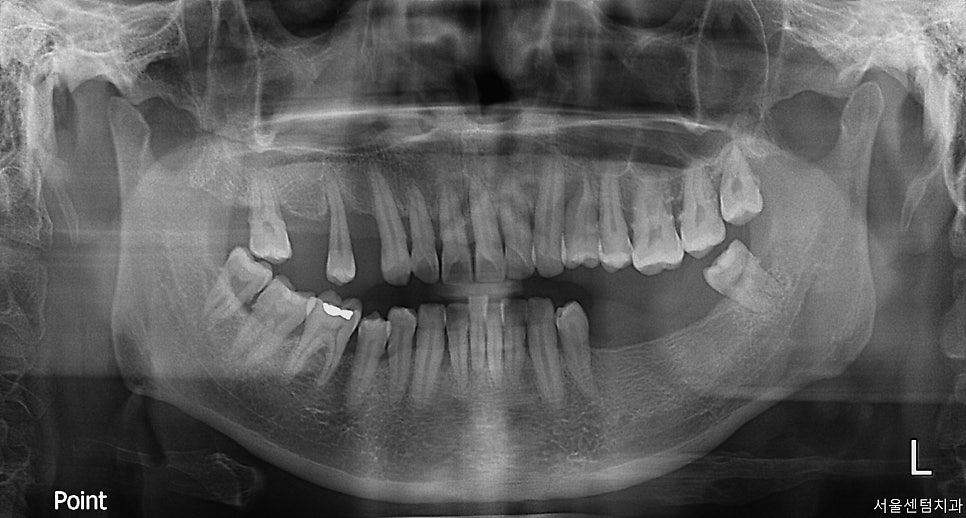

40대의 여성 환자분

첫 내원은 더위가 가시고

가을이 찾아오기 시작할 즈음이었죠.

처음 오셨을 때 이미 어금니가

여러개 없는 상황이었습니다.

일단 파노라마 찍고 치근단 엑스레이

CT까지 확실히 촬영한 후 확인했습니다.

자세히 살펴보면 치석도 치아 사이사이

치간 사이에 꽤나 많은 케이스입니다.

그렇다 보니 당연히 잇몸의 건강 또한

좋은 상황은 아니었고요.

전반적으로 치아관리가 잘 되고 있는

케이스로 보기는 어렵습니다.